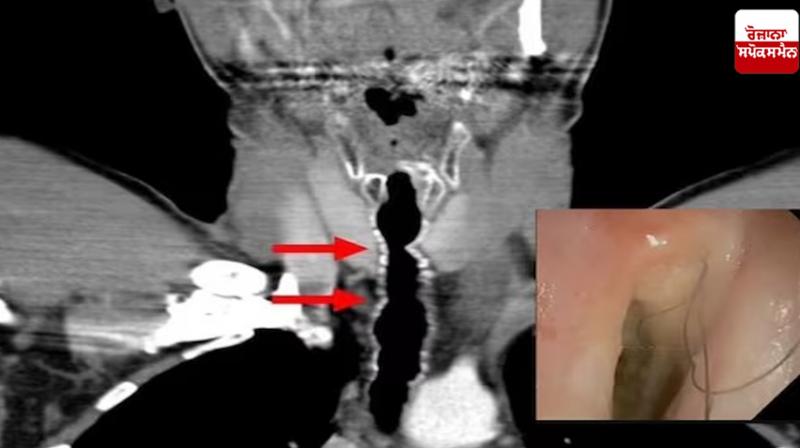

ਡਾਕਟਰਾਂ ਨੇ ਦੱਸਿਆ ਕਿ ਇਸ 54 ਸਾਲਾ ਵਿਅਕਤੀ ਨੂੰ ਸਾਹ ਲੈਣ ਵਿੱਚ ਤਕਲੀਫ਼ ਅਤੇ ਪੁਰਾਣੀ ਖੰਘ ਦੀ ਸ਼ਿਕਾਇਤ ਸੀ। ਆਸਟ੍ਰੀਆ ਦੇ ਇਸ ਮਰੀਜ਼ ਨੇ ਦਾਅਵਾ ਕੀਤਾ ਕਿ ਉਸ ਨੇ 1990 ਵਿੱਚ ਸਿਗਰਟ ਪੀਣੀ ਸ਼ੁਰੂ ਕਰ ਦਿੱਤੀ ਸੀ, ਜਦੋਂ ਉਹ 20 ਸਾਲ ਦਾ ਸੀ। ਉਸ ਦੌਰਾਨ ਉਸ ਨੇ ਖੰਘ ਕੇ ਇਕ ਵਾਰ ਵਾਲ ਕੱਢਣ ਦੀ ਘਟਨਾ ਬਾਰੇ ਵੀ ਦੱਸਿਆ ਸੀ। ਅਜਿਹੇ 'ਚ ਡਾਕਟਰਾਂ ਨੇ ਉਸ ਦੀ ਸਾਹ ਪਾਈਪ 'ਚ ਛੋਟਾ ਕੈਮਰਾ ਭੇਜ ਕੇ ਉਸ ਦੇ ਗਲੇ ਦੀ ਜਾਂਚ ਕਰਨ ਦਾ ਫੈਸਲਾ ਕੀਤਾ, ਜਿੱਥੇ ਉਨ੍ਹਾਂ ਦੇਖਿਆ ਕਿ ਵਿਅਕਤੀ ਦੇ ਗਲੇ 'ਚ ਕਾਲੇ ਵਾਲ ਉੱਗ ਰਹੇ ਸਨ।

ਡਾਕਟਰਾਂ ਨੇ ਉਸ ਦੇ ਮੂੰਹ 'ਚੋਂ ਵਾਲ ਕੱਢ ਦਿੱਤੇ ਅਤੇ ਵਾਲਾਂ 'ਚ ਬੈਕਟੀਰੀਆ ਪਾਏ ਜਾਣ 'ਤੇ ਉਸ ਨੂੰ ਐਂਟੀਬਾਇਓਟਿਕ ਦਵਾਈਆਂ ਵੀ ਦਿੱਤੀਆਂ ਗਈਆਂ। ਇਸ ਕਾਰਨ ਵਿਅਕਤੀ ਨੂੰ ਆਰਜ਼ੀ ਰਾਹਤ ਮਿਲੀ। ਇਹ ਸਾਲ 2010 ਦੀ ਗੱਲ ਹੈ ਪਰ ਉਸਦੀ ਸਮੱਸਿਆ ਕਦੇ ਖਤਮ ਨਹੀਂ ਹੋਈ। ਅਗਲੇ 14 ਸਾਲਾਂ ਤੱਕ ਹਰ ਸਾਲ ਵਾਲ ਵਾਪਸ ਆਉਂਦੇ ਰਹੇ। ਇਸ ਕੇਸ ਵਿੱਚ, ਇੱਕ ਬਹੁਤ ਹੀ ਦੁਰਲੱਭ ਸਥਿਤੀ ਦਾ ਇਲਾਜ ਕੀਤਾ ਗਿਆ ਸੀ ਜਿਸਨੂੰ ਐਂਡੋਟਰੈਚਲ ਵਾਲਾਂ ਦਾ ਵਾਧਾ, ਜਾਂ ਗਲੇ ਵਿੱਚ ਵਾਲਾਂ ਦਾ ਵਾਧਾ ਕਿਹਾ ਜਾਂਦਾ ਹੈ।

ਵਿਅਕਤੀ ਦਾ ਇਲਾਜ ਕਰ ਰਹੇ ਡਾਕਟਰਾਂ ਦਾ ਕਹਿਣਾ ਹੈ ਕਿ ਉਹ ਪੱਕੇ ਤੌਰ 'ਤੇ ਨਹੀਂ ਕਹਿ ਸਕਦੇ ਪਰ ਗਰਦਨ 'ਤੇ ਵਾਲਾਂ ਦਾ ਵਧਣਾ ਸ਼ਾਇਦ ਉਸ ਦੀ ਸਿਗਰਟ ਪੀਣ ਦੀ ਆਦਤ ਕਾਰਨ ਸੀ। ਅਮਰੀਕਨ ਜਰਨਲ ਆਫ ਕੇਸ ਰਿਪੋਰਟਸ ਵਿੱਚ ਇਸ ਵਿਅਕਤੀ ਦੀ ਬਿਮਾਰੀ ਸਬੰਧੀ ਇੱਕ ਲੇਖ ਵੀ ਪ੍ਰਕਾਸ਼ਿਤ ਹੋਇਆ ਸੀ। ਆਸਟ੍ਰੀਆ ਤੋਂ ਆਏ ਡਾਕਟਰਾਂ ਨੇ ਇਸ ਵਿਅਕਤੀ ਦੇ ਗਲੇ 'ਚ ਵਾਲਾਂ ਦੇ ਵਧਣ ਬਾਰੇ ਦੱਸਿਆ ਕਿ ਸਿਗਰਟ ਪੀਣ ਨਾਲ ਗਲੇ 'ਚ ਸੋਜ ਆ ਸਕਦੀ ਹੈ, ਜਿਸ ਕਾਰਨ ਸੈੱਲ ਵਾਲਾਂ ਨੂੰ ਰੋਮ 'ਚ ਬਦਲ ਸਕਦੇ ਹਨ। ਅਜਿਹੇ 'ਚ ਜਦੋਂ ਵੀ ਡਾਕਟਰਾਂ ਨੇ ਦੇਖਿਆ ਤਾਂ ਆਦਮੀ ਦੀ ਗਰਦਨ 'ਤੇ ਛੇ ਤੋਂ ਨੌਂ ਦੋ ਇੰਚ ਦੇ ਵਾਲ ਉੱਗ ਰਹੇ ਸਨ। ਕੁਝ ਵਾਲ ਵੀ ਉਸ ਦੇ ਵਾਇਸ ਬਾਕਸ ਵਿੱਚ ਫਸਣ ਲੱਗੇ ਅਤੇ ਉਹ ਉਸਦੇ ਮੂੰਹ ਵਿੱਚ ਜਾ ਚੜ੍ਹੇ।